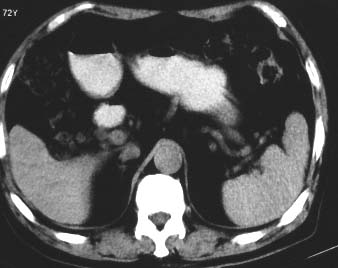

男 56 腹部不舒

典型肝硬化:1、肝各叶大小的比例失常;2、肝表面明显凹凸不整,边缘变钝;3、肝实质密度一般与正常肝无明显改变;4、肝裂增宽;5、门静脉增宽,脾静脉扩张扭曲;6、脾脏虽然不大,但不是所以肝硬化的脾脏都增大。

典型肝硬化:1、肝各叶大小的比例失常;2、肝表面明显凹凸不整,边缘变钝;3、肝实质密度一般与正常肝无明显改变,但肝右叶似可见再生结节影;4、肝裂增宽;5、门静脉增宽,脾静脉扩张扭曲;6、脾脏增大. 脾脏大小的标准有:1脾脏的左右径(大于5个肋单元) 2脾脏的宽度 3脾脏的上下径(超过肝下缘) 请参考.

典型肝硬化:1、肝各叶大小的比例失常;2、肝表面明显凹凸不整,边缘变钝;3、肝实质密度一般与正常肝无明显改变,但肝右叶似可见再生结节影;4、肝裂增宽;5、门静脉增宽,脾静脉扩张扭曲;6、脾脏增大.

典型肝硬化:1、肝各叶大小的比例失常;2、肝表面明显凹凸不整,边缘变钝;3、肝实质密度一般与正常肝无明显改变,但肉眼观察与脾胀密度低或等密度;4、肝裂增宽;5、门静脉增宽,脾静脉扩张扭曲;6、脾脏增大.

典型肝硬化:1、肝各叶大小的比例失常;2、肝表面明显凹凸不整,边缘变钝;3、肝实质密度一般与正常肝无明显改变,4、肝裂增宽;5、门静脉增宽,脾静脉扩张扭曲;6、脾脏增大.

就本病例而言,楼上的战友可能有点优柔寡断。如果是先天性肝脏形态异常,那么它的密度异常就不符合了吧?仔细看,的确如多位战友所言,肝脏密度不均匀,有再生结节,考虑肝硬化应该不会出错。当然,楼上战友那样写报告是最保险的,我也会这么写,我们在实际工作中都应该学会自我保护。

ct表现符合肝硬化,建议增强扫描.